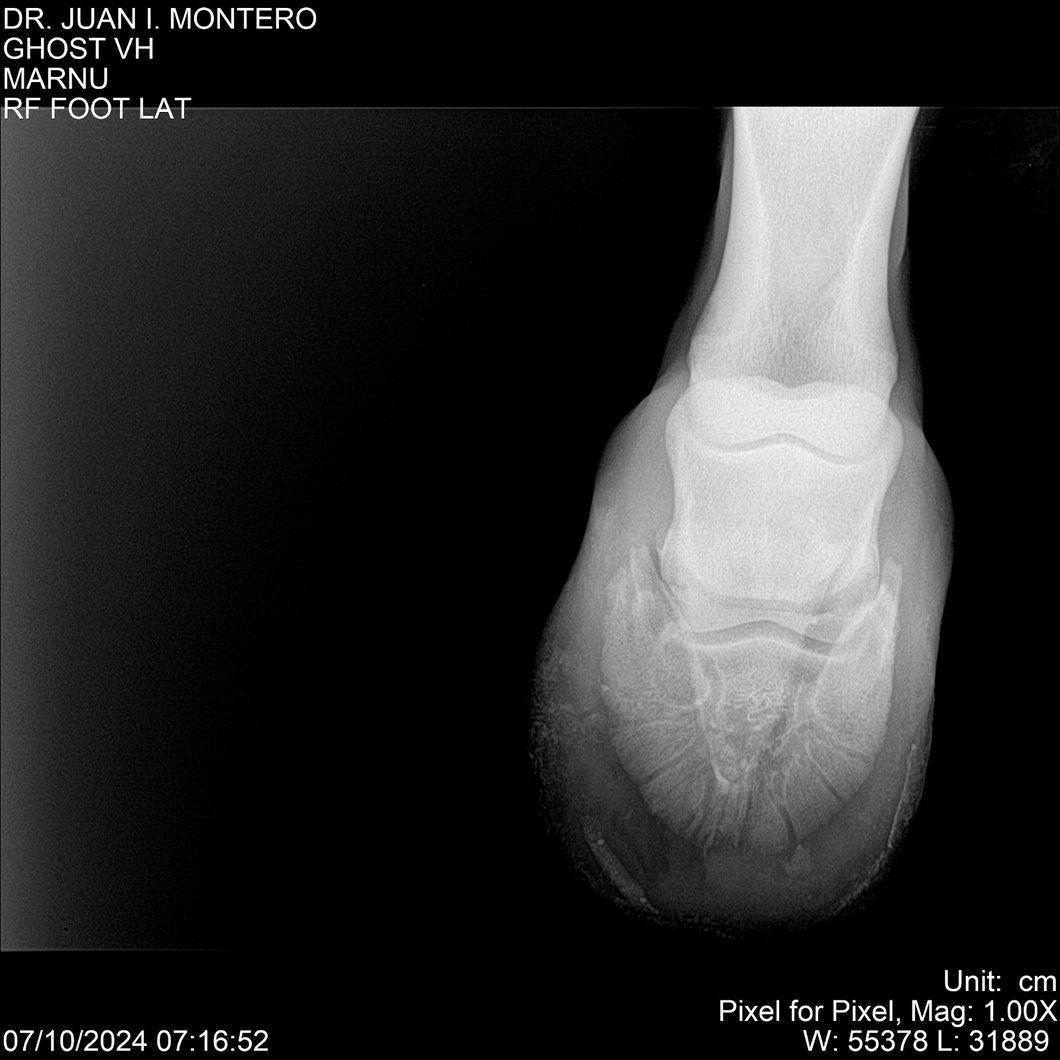

LOTE 15, GHOST VH 🔥 🔥 🔥 Lote Anterior Volver al remate Lote Siguiente Ficha Contacto Montevideo - Ficha del Lote Identificador: #282525 Categoría: Yeguarizos Montevideo - 69 Visualizaciones ClicData Contacto Empresa: Abelenda N. R., Walter Hugo Nombre*: Teléfono* : E-mail* : Mensaje Enviar Registrese gratis Este contenido Exclusivo está disponible sólo para usuarios registrados Ingresar